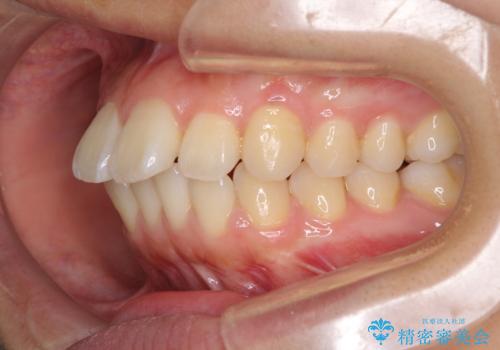

- 前方に傾斜した上下の前歯を気にして来院された患者様です。

唇の閉じにくさや横顔のシルエットが気になるような突出感ではなかったため、インビザラインを用いて、歯列の遠心移動とIPR(歯と歯の間を削る)により前歯の傾斜を改善していくこととしました。

スムーズに終了すると思われましたが、インビザライン矯正独特の奥歯が咬み合わない状態が続き、更には遠方へ転居されたこともあり、治療期間は長引いてしまいました。